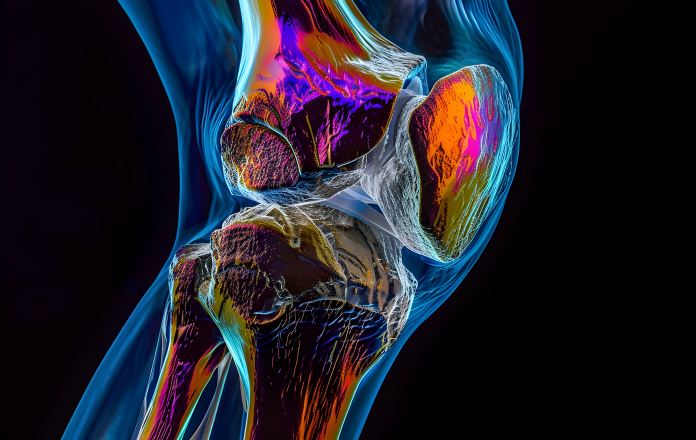

Well, take a look at this picture:

This is the most dangerous acid in the world.

It’s called “fluoroantimonic acid” and it can burn through almost anything including glass, ceramic materials, and even some metals.

And as scary as this may sound, YOU actually have a similar acid building up and bubbling inside your joints…

And when this acid builds up…

It eats away at your joints just like that acid eating through sheet metal…

And over time this literally works to DISSOLVE the cartilage and other cushioning tissues from the inside out.

As a result, your joints suffer and you experience aches, stiffness, and burning…